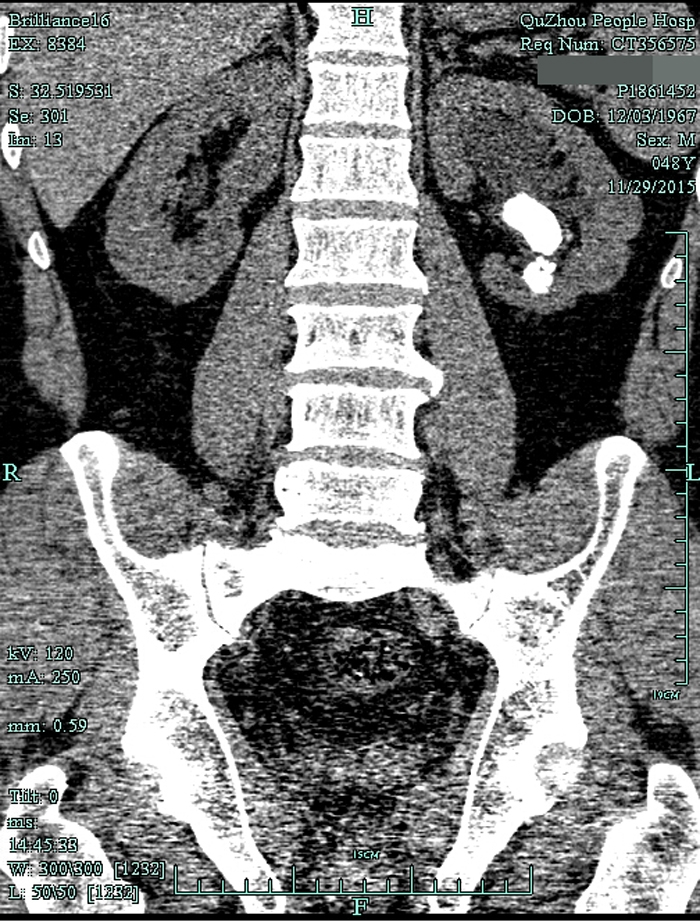

??? 一查泌尿系CT,兄弟倆都是左腎鹿角型結(jié)石,而且已經(jīng)有腎積水。根據(jù)CT檢查結(jié)果以及結(jié)石體積大(3cm)、質(zhì)地硬的特點(diǎn),萬醫(yī)師建議兩人行經(jīng)皮腎鏡碎石取石術(shù),才能將結(jié)石清理干凈。

術(shù)前CT1

術(shù)前CT2